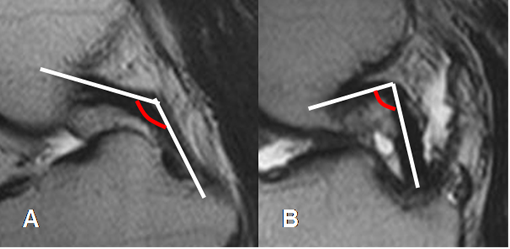

La ruptura completa del LCA, es diagnosticada mediante los signos primarios. (11). El principal, es la discontinuidad de las fibras (2, 35) y el otro es su orientación. Hay horizontalización, con disminución del ángulo de inclinación con la tibia, el cual es menor de 40º y el ángulo con la línea de Blumensaat, de vértice inferior y valor positivo mayor de 15º. (11). (Fig 100 y 101).

Fig 101. Ruptura del LCA.

A y B: RM sagital en T2. Signos de ruptura, con disminución del ángulo de inclinación tibial en A y ángulo con la línea intercondílea, de vértice inferior en B.